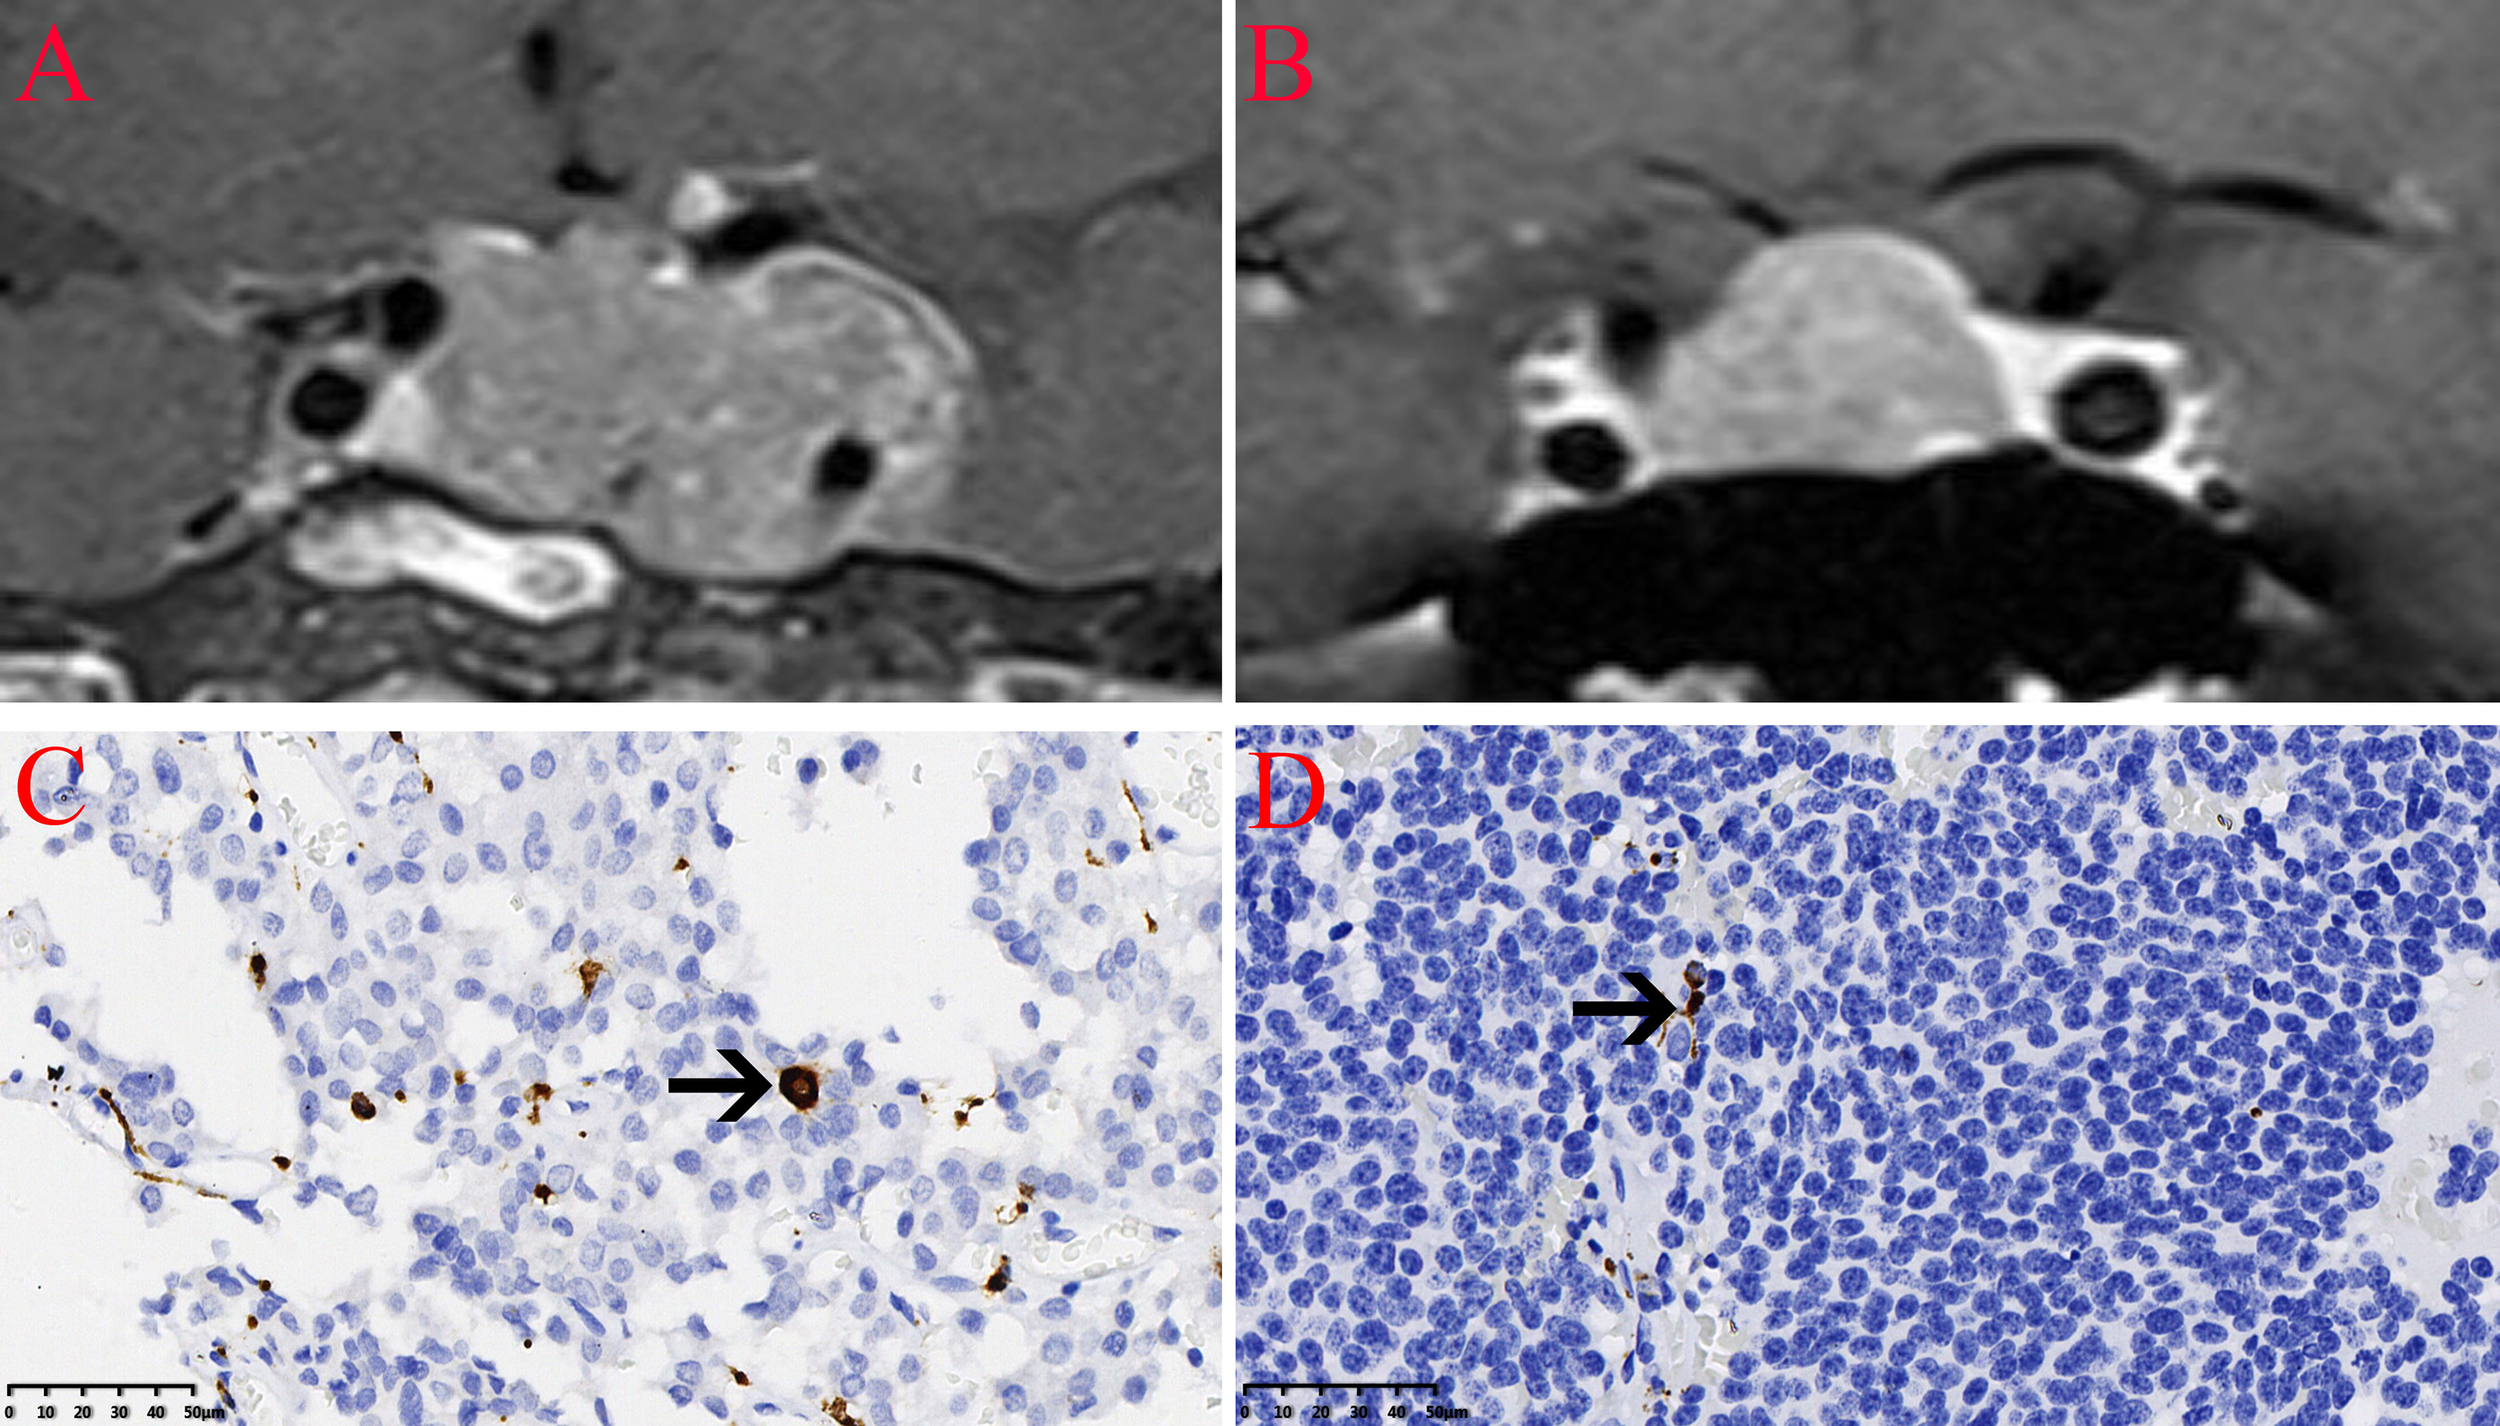

The expression of the M2 macrophage marker CD206 and presence of M2 macrophages in NFPA were evaluated using immunohistochemistry (Figure 5). The number of CD206-positive cells in invasive NFPA (12.66 ± 4.80 cells/field) was higher than that in non-invasive NFPA (4.00 ± 3.02 cells/field, p < 0.001) (Figure 6).

Infiltration of CD206 macrophages in nonfunctioning pituitary adenomas NFPAs. The CD206 macrophages are indicated by the arrow. (A) Coronal contrast-enhanced image showing invasive pituitary adenomas. (B) Coronal contrast-enhanced image showing non-invasive pituitary adenomas. (C) Infiltration of CD206 macrophages in invasive NFPAs. (D) Infiltration of CD206 macrophages in non-invasive NFPAs.